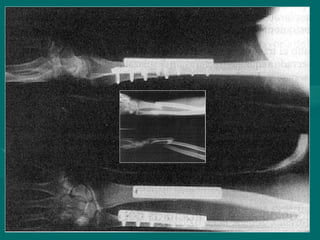

Fractura Essex-Lopresti

• Fractura conminuida de la cabeza

Fractura conminuida de la cabeza

radial asociada con subluxacion de la

articulacion radioulnar distal

• Usualmente asociado con la desviacion

Usualmente asociado con la desviacion

radial de la mano

• En las fracturas conminutas

En las fracturas conminutas

de la cabeza de radio debe ser

indispensable una examen radiológico

de la muñeca

Fractura Essex-Lopresti Fractura Essex-Lopresti •Fractura conminuida de la cabeza Fractura conminuida de la cabeza radial asociada con subluxacion de la radial asociada con subluxacion de la articulacion radioulnar distal articulacion radioulnar distal • Usualmente asociado con la desviacion Usualmente asociado con la desviacion radial de la mano radial de la mano • En las fracturas conminutas En las fracturas conminutas de la cabeza de radio debe ser de la cabeza de radio debe ser indispensable una examen radiológico indispensable una examen radiológico de la muñeca de la muñeca